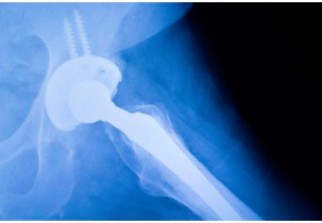

Arthrose : Les prothèses de hanche vont-elles disparaître ?

Les prothèses de hanche pourraient bientôt devenir de l'histoire ancienne et céder la place à un dispositif médical composé de cartilage issu de cellules souches.

Une équipe de chercheurs de l'Université de Washington (Etats-Unis) vient d'apporter un nouvel espoir aux patients qui souffrent d'arthrose. Ceux-ci viennent en effet de mettre au point une hanche artificielle composée de cartilage issues de cellules souches.

Ce cartilage "vivant" est la première alternative réelle à la prothèse de hanche en métal ou en céramique que l'on pose aujourd'hui chez les personnes qui souffrent d'arthrose . Cette technique pourrait un jour apporter un soulagement aux patients de moins de 50 ans et pour lesquels l'implantation d'une articulation qui va durer moins de 20 ans est rarement une option.

La technique utilisée par les chercheurs américains utilise la technologie 3D pour créer un moule à la forme exacte de l'articulation du patient. Ce moule est ensuite recouvert de cartilage créé à partir des propres cellules souches du patient prises dans la graisse sous-cutanée. Les médecins font également appel à la thérapie génique pour que ce nouveau cartilage libère des molécules anti-inflammatoires empêchant toute nouvelle poussée d'arthrose et toute destruction du nouveau cartilage.Les implants sont suffisamment solides pour supporter des charges allant jusqu'à 10 fois le poids du corps d'un patient.